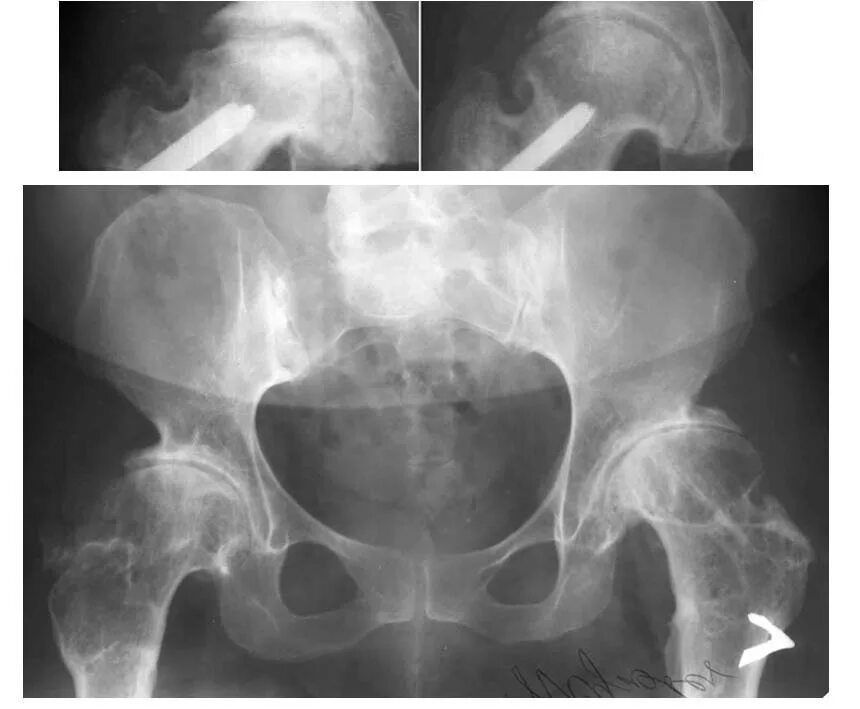

Некроз головки тазобедренного сустава 2